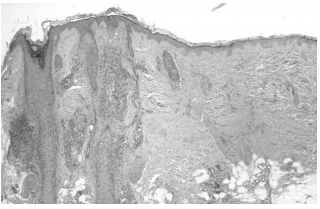

Рис. 9. Лимфогистиоцитарные инфильтраты вокруг расширенных устьев волосяных фолликулов. Эпидермис между фолликулами не изменен. Окраска гематоксилином и эозином, ув. ×40

Рис. 10. Тот же препарат, ув. ×100, ув. ×400. Изменения эпителия устья волосяного фолликула: вакуолизация и скваматизация клеток базального слоя, гипергранулез, ортогиперкератоз, участки атрофии